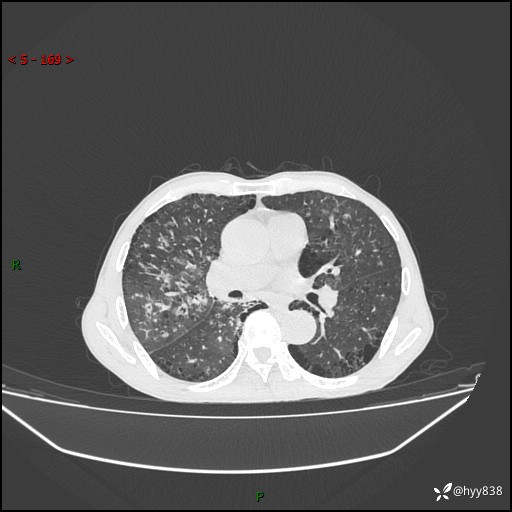

胸部CT平扫